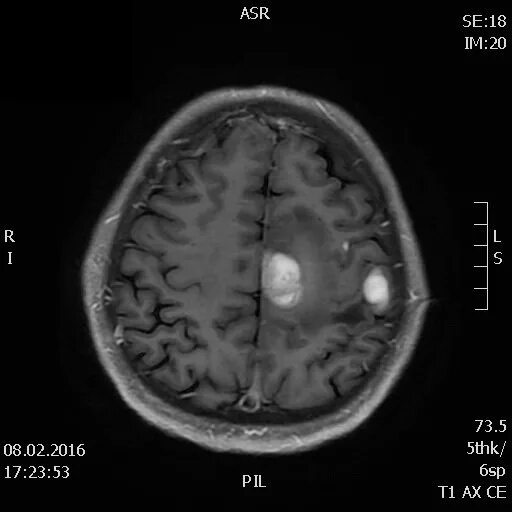

Метастазы в головном мозге мкб